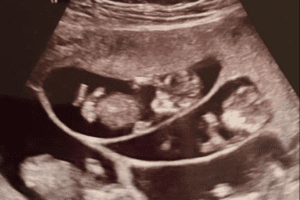

En la ecografía se vieron seis sacos placentarios. Eran seis los bebés que estaban en el vientre de Courtey. “Fue la conmoción de nuestras vidas”, dijo la mujer, quien aseguró que al principio, al saber la noticia, se angustiaron un poco y se preocuparon. Llevar seis bebés en el vientre es algo arriesgado. Courtney se sentía algo molesta y asustada, pero finalmente, la noticia fue alegrando poco a poco a la familia. Así, en pocos meses, la pareja recibirá a seis hijos más, aparte de los tres que ya tienen.